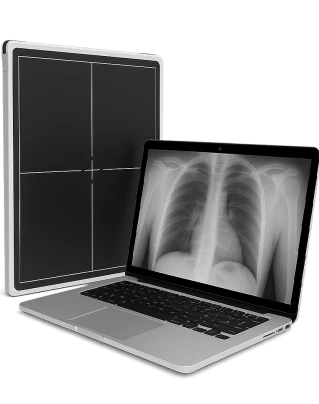

Рентген позвоночника — это неинвазивный метод диагностики, который с помощью рентгеновских лучей позволяет визуализировать кости, суставы и межпозвонковые диски для оценки состояния позвоночного столба и выявления патологий.

Методика помогает обнаружить искривления, смещения, переломы, остеохондроз, артроз и другие дегенеративные изменения. Снимки фиксируют форму и высоту позвонков, расстояние между ними, наличие костных наростов и уплотнений.

Рентгенограмма показывает взаимное расположение костных элементов, состояние межпозвонковых дисков и контуры суставных поверхностей. При необходимости врач проводит снимки с функциональными пробами, чтобы оценить подвижность и степень нестабильности позвоночного сегмента.